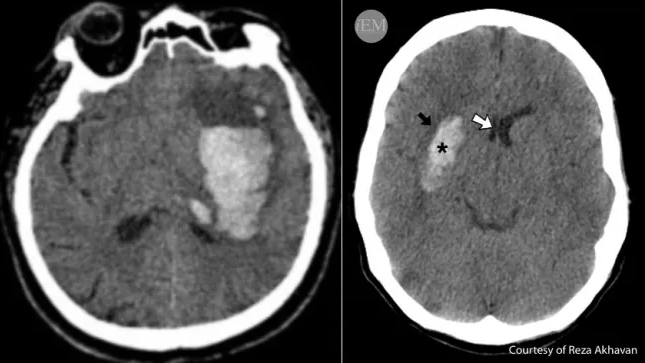

Basal Ganglia Hemorrhage

By: Fernanda Calienes-Cerpa, MD and Erik Fisher, MD

Abnormal Brain Imaging

By: Laura Tormoehlen, MD, FACMT, FAAN and Jeff C. Miller, MD